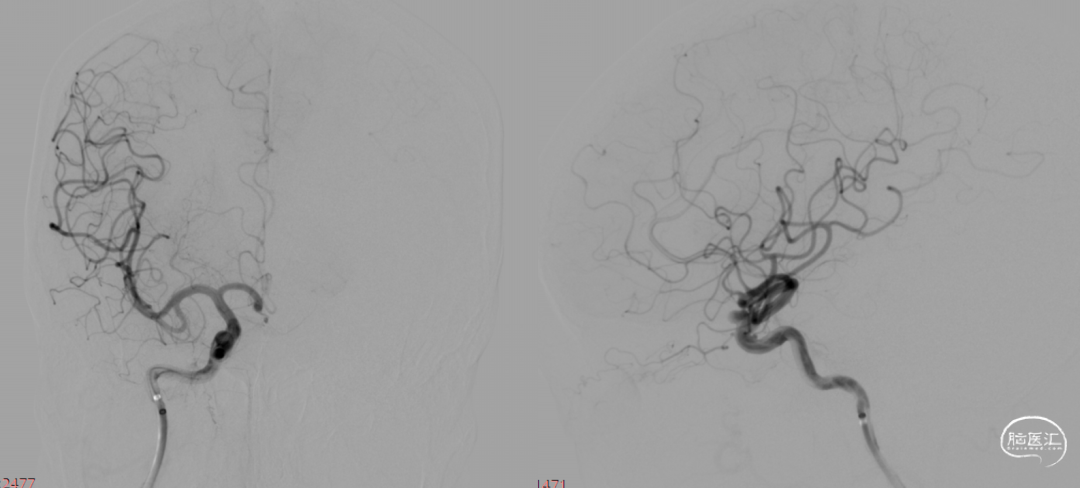

疏松填塞弹簧圈后正侧位造影。

术后即刻。

术后即刻,可见动脉瘤瘤腔内血液滞留明显。

术后即刻,正侧位造影。